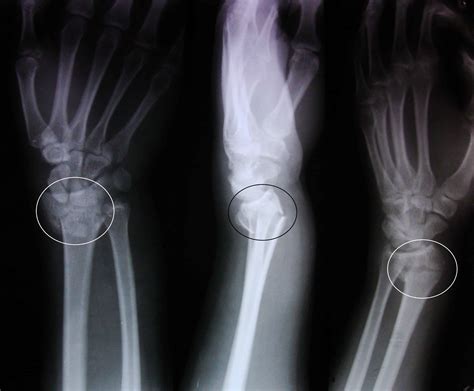

Diagnosis of a Colles Fracture is typically made through:

• Clinical examination, including inspection and palpation of the wrist.

• Radiographic imaging, which may include anteroposterior (AP) and lateral views of the wrist to visualize the fracture and assess the degree of displacement.